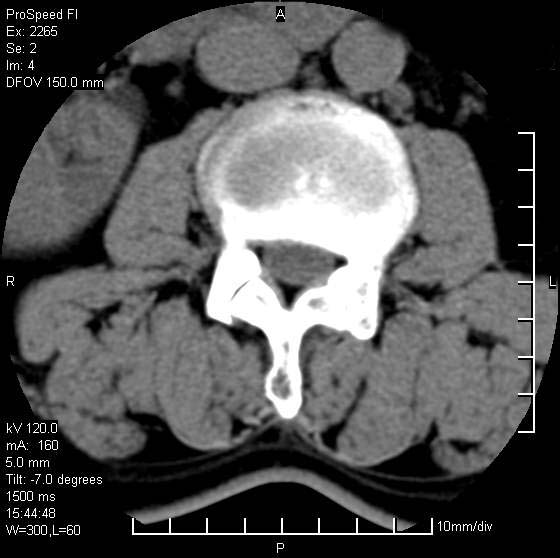

以下是引用qiushi在2007-8-22 17:26:00的发言:[br]没骨窗![br] 1、 l5~s1间盘膨出伴轻度突出(中央型)、变性。[br] 2、l4~5间盘膨出伴突出(右侧远外侧型)。[br] 3、l3~4间盘膨出。[br] 4、腰椎退行性变。[br]

以下是引用随缘的人在2007-8-22 20:56:00的发言:[br]腰椎退行性变:1。l4/5,l5/s1膨出[br] 2。l5/s1间盘退行性变 [br] 3。腰椎骨质增生

以下是引用liaizhi在2007-8-22 22:13:00的发言:[br]1,l4-5锥间盘膨出,2,l5-s1椎间盘膨出并退变(椎间盘呈真空征);3,血管瘤(椎体骨小梁稀疏粗大)?